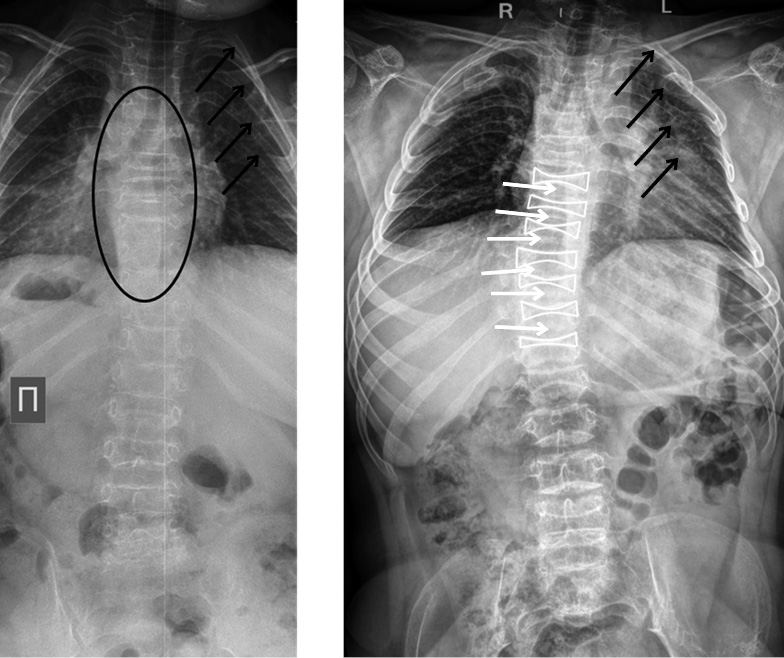

Spinal radiographs of both patients showed increased thoracic kyphosis, decreased height of vertebral bodies (particularly in the central and anterior regions), “fish vertebrae” contours, anisospondylia (varying height of adjacent deformed vertebral bodies), more vertical positioning of ribs (primarily in the upper thorax), and a general decrease in vertebral body BMD (Figs. 2 and 3).

Fig. 3. Radiographs of the spine in direct projection of patients 1 and 2: reduction in the height of vertebral bodies, predominantly in the central part, with the formation of “pseudobabcular” vertebral contours (indicated by white lines), most pronounced at the apex of kyphosis (circled by a black line); relative enlargement of the central parts of the intervertebral discs (white arrows); more vertical positioning of the ribs, predominantly in the upper parts of the thorax (black arrows)